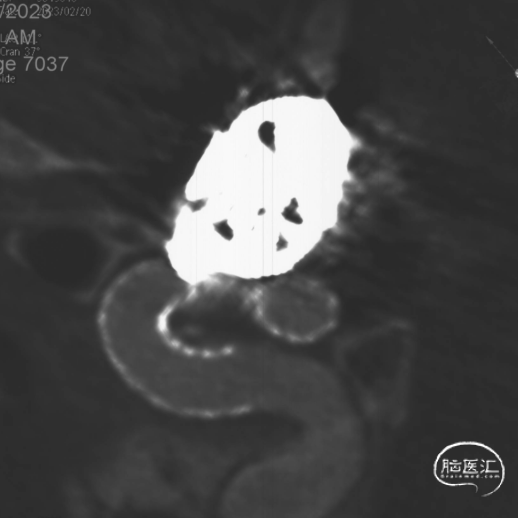

Vaso CT重建 支架打开、贴壁良好。